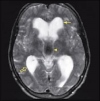

Различают сообщающуюся или открытую и окклюзионную или закрытую врожденную гидроцефалию. При открытой форме гидроцефалии наблюдается расширение всех желудочковых систем головного мозга. При этом препятствия для тока цереброспинальной жидкости нет. Закрытая форма гидроцефалии характеризуется наличием новообразований, спаечных процессов, каких-либо аномалий развития ликвороносной системы, при которых существует препятствие для нормального ликворотока внутри желудочковой системы головного мозга.

Из-за внутричерепной травмы в ходе родов в первые месяцы жизни ребенка может развиться приобретенная гидроцефалия. Внутричерепная травма в ходе родов приводит к возникновению внутричерепных кровоизлияний, что также может явиться причиной гидроцефалии. Кроме этого, причиной развития гидроцефалии могут стать перенесенные организмом ребенка интоксикации, менингиты, менингоэнцефалиты, которые приводят к нарушению всасывания цереброспинальной жидкости. В норме количество жидкости в мозге является постоянным, поскольку ее показатель уравновешивается постоянными процессами ее производства и всасывания. Это обеспечивает и постоянство внутричерепного давления. При нарушении же баланса и накоплении цереброспинальной жидкости происходит увеличение одного или нескольких желудочков мозга, что ведет к повышению внутричерепного давления.

Для подтверждения диагноза «гидроцефалия» проводят неврологическое обследование, компьютерную томографию, нейросонографию, магнитно-резонансную томографию. После установления причины возникновения гидроцефалии принимается решение о проведении той или иной формы лечения. Чаще всего прибегают к хирургическому вмешательству, поскольку консервативное лечение не всегда дает при таком заболевании хороший результат.